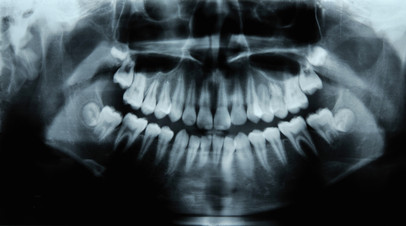

Врач-ортодонт Андрей Жук рассказал, что при отсутствии лечения флюса инфекция может распространиться на кости челюсти и мягкие ткани.